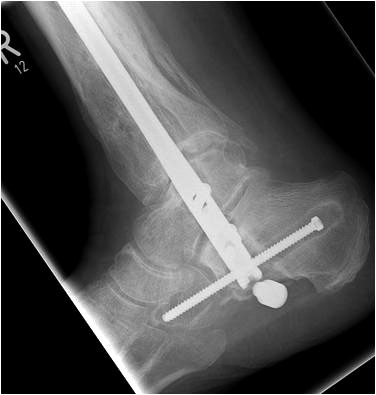

• Primäre oder posttraumatische Arthrose des OSG und USG (Abbildung 1, Abbildung 2).

• Revision einer gescheiterten Fusion des OSG/ USG (Abbildung 3, Abbildung 4).

• Pseudarthrosen (Abbildung 5, Abbildung 6).